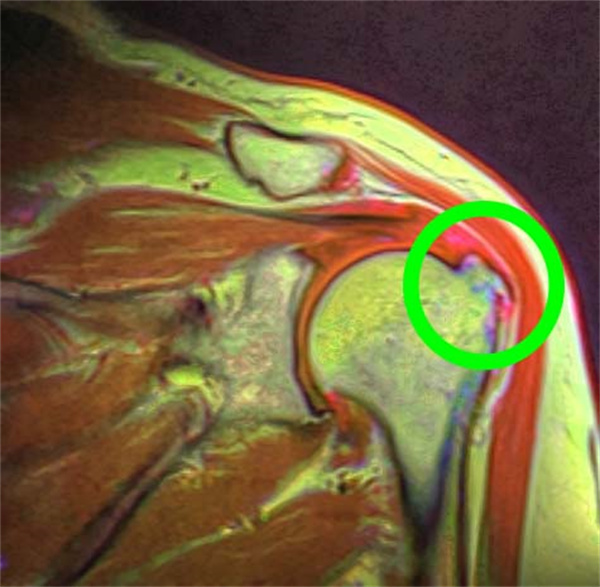

骨刺主要的症狀為活動時,關節感到疼痛不適,基本上只要有關節的地方就可能會有骨刺的產生,臨床上骨刺常發生的位置像是頸椎、腰椎、骨盆、膝蓋、肩關節、腳踝、手指頭的小關節,而發生在各關節的骨刺,造成的不適感也不盡相同。